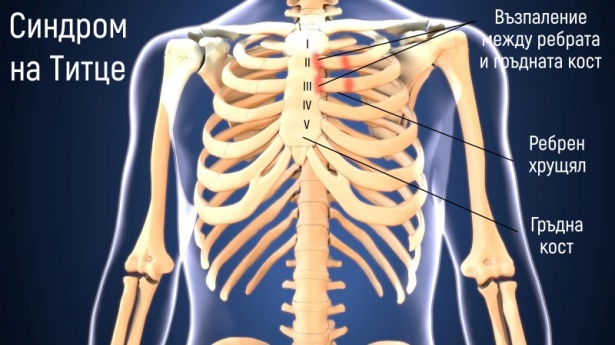

Синдром на хондрокосталните съчленения , познат като синдром на Титце (Tietze), представлява рядко състояние, което се характеризира с единично или множествено задебеляване на предната гръдна стена, най-често на ниво 2-ро и 3-то ребро. В основата му е доброкачествено асептично възпаление в областта на преходите от ребро към ребрен хрущял, ребрен хрущял към гръдна кост или ключица към гръдната кост. Основните симптоми са болка и локален оток. Болката се провокира от натиск, кашлица, усилено дишане и може да се разпространява към други части на тялото. Именно поради тази причина първоначално състоянието може да се диагностицира погрешно като белодробен или сърдечен проблем. Диагнозата се поставя на основата на физикален преглед, изключване на други състояния и образни изследвания. Лечението е главно консервативно. Прилагат се противовъзпалителни препарати, аналгетици и се ограничават факторите провокиращи болката. В повечето случаи заболяването отминава за около 3 месеца.

Синдромът на Титце и костохондритът са сходни състояния, засягащи мястото на свързване на ребрата с гръдната кост. Разликата между тях се изразява най-вече в наличието на оток на ребрените хрущяли и местоположението. При синдромът на Титце се наблюдава оток на ребрените хрущяли, което не се проявява при костохондрит. Освен това, костохондритът засяга областта от 2-ро до 5-то ребро, докато синдромът на Титце обикновено засяга 2-ро или 3-то ребро. И двете състояние не са сериозни и често се лекуват по един и същи начин.